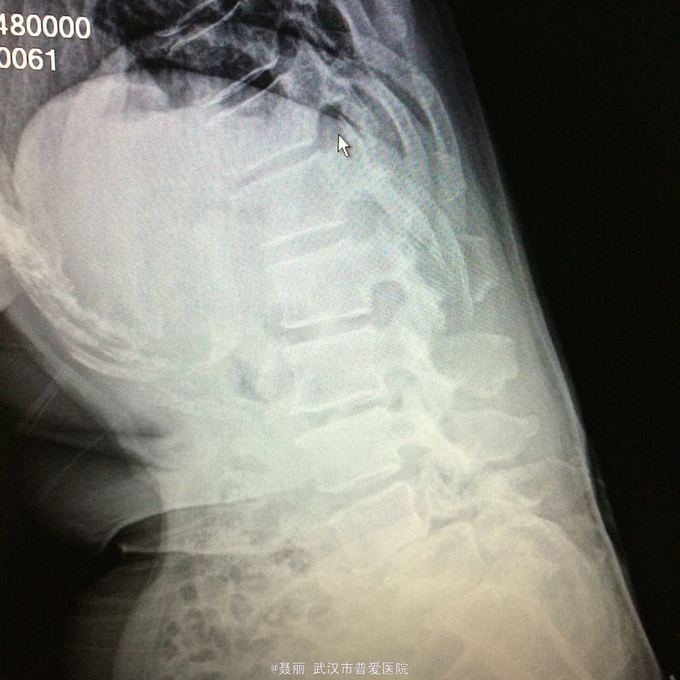

患者,女,51岁。 反复腰痛并间歇性跛行5年余,加重并左侧臀部2月余。 患者于5年前无明显诱因外伤诱因出现腰痛,不伴有双下肢麻木、乏力及间歇性跛行,卧床休息后好转,间歇发作,进行性加重。 既往史:有高血压病、糖尿病病史,否认有药物过敏

:L4/5棘突间轻压痛,叩痛,棘间左侧椎旁压痛;双下肢肌力、肌张力正常,病理反射未引出。 门诊资料:外院行腰椎CT检查示:L3-S1椎间盘膨出,L4椎弓崩裂并向前滑脱(重度)椎管狭窄。 入

入院诊断:、腰椎滑脱(L4/5 峡部裂性) 诊疗计划:1:完善有关检查2卧床休息,行改善微循环、3.腰椎后路复位减压植骨融合术

行改善微循环、3.腰椎后路复位减压植骨融合术 腰椎滑脱(L4/5 Ⅱ度)、腰椎管狭窄症(L3/4)、腰椎间盘突出症(L5/S1)查体双下肢感觉、活动无明显异常。双下肢末梢血液循环可。换药见伤口对合良好,无明显红肿渗出。伤口已拆线。嘱加强双下肢活动及功能锻炼,避免下肢深静脉血栓,主动及被动四肢活动,预防血静脉及床褥形成,加强腰背肌锻炼,适量康复功能锻炼。一个月后来复查伤口愈合好,疼痛没有,活动可